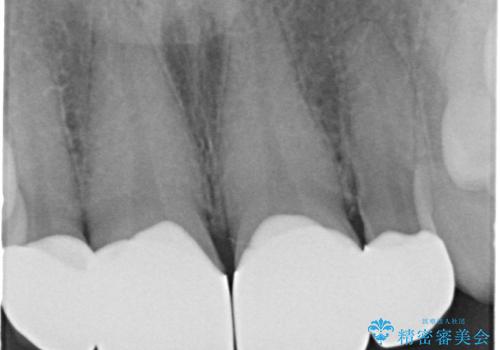

歯の向きは悪くなかったため、神経は取らずに治療しました。